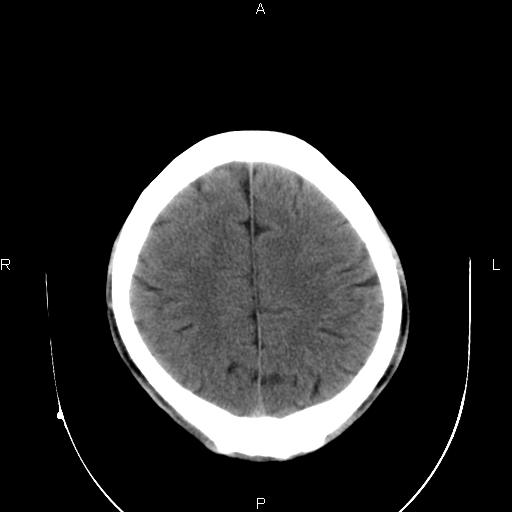

男性,40岁,反复头痛,视物旋转一月余,无呕吐,pe未见明确异常。

我的问题是上矢状窦高密度怎么解释?请各位专家不吝指教,谢谢!

可结合增强或mrv检查除外上矢状窦血栓。